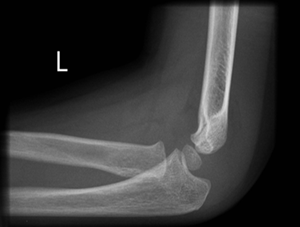

A posterior fat pad is always abnormal |